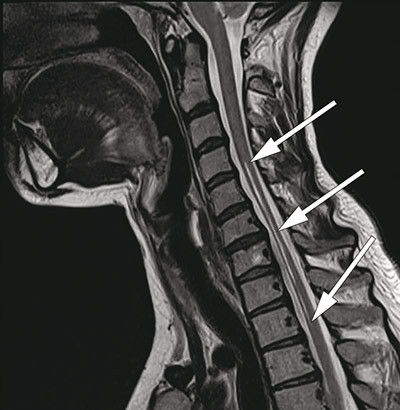

MRI of the spinal cord showed marked atrophy from C4 to Th2 and two longitudinal symmetrical T2-weighted hyperintense lesions from C2 to Th2 (<<<. 3, Fig. 4), confined to the anterior horn area of the medulla. The changes were not considered consistent with syringomyelia, demyelinating plaques, tumour or transverse myelitis. MRI of the head was normal.

Figure 4  Axial T2-weighted MRI of cervical medulla with symmetrical hyperintense lesions localised to the site of the…

Figure 4 Axial T2-weighted MRI of cervical medulla with symmetrical hyperintense lesions localised to the site of the anterior horn cells